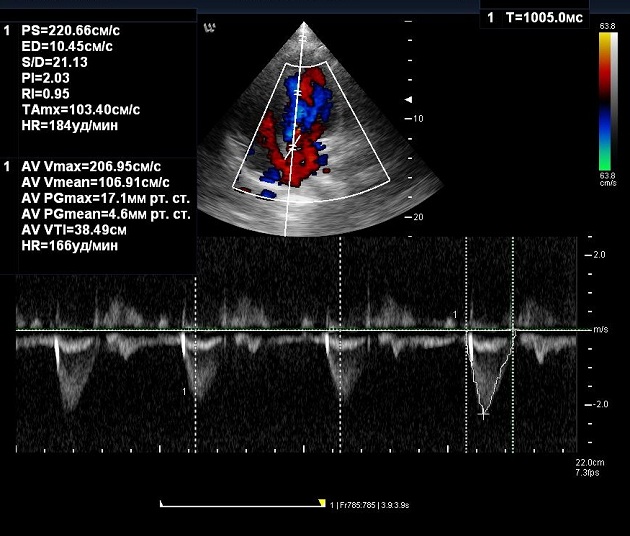

Заключился как, сочетанный аортальный порок: функционально двустворчатый аортальный клапан с незначительным клапанным стенозом и недостаточностью 1-2 ст.

Скорость ВТЛЖ около 1 м/с (фото не сохранил). На аортальном клапане ускорение кровотока до 2,06-2,2 м/с. Тахикардии нет, ЧСС - 59 в мин.Однозначно имеется аортальная недостаточность до 2 ст. Непонятно на каком основании выставляется аортальный стеноз? Какова скорость в ВТЛЖ и скорость трансмитрального кровотока? Есть ли тахикардия? У молодых людей на фоне тахикардии можно получить очень высокие скорости на клапанах! Почему-то все забыли о площади аортального отверстия